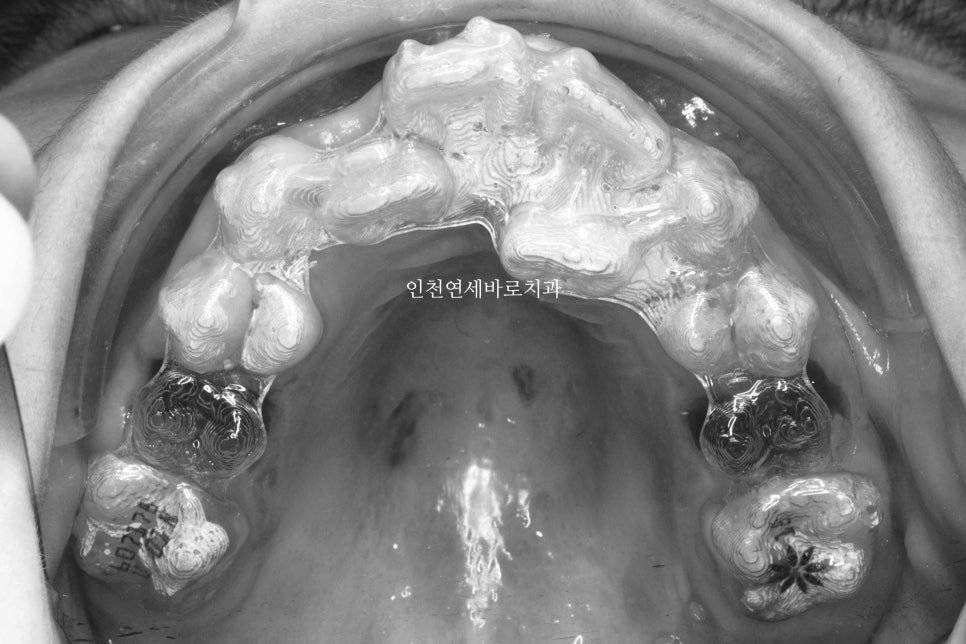

처음 시작하고 약 7개월 정도가 지났을때의 모습입니다. 아직은 삐뚠 치열이 남아있지만, 어느정도 정리가 되어가고 있네요